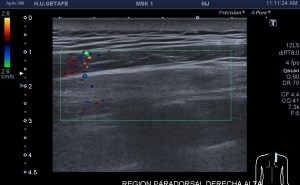

Los vientres anteriores de los Músculos Digástricos derecho e izquierdo forman los bordes laterales del triángulo submentoniano, mira:

En este triángulo lo que vas a encontrar son ganglios.